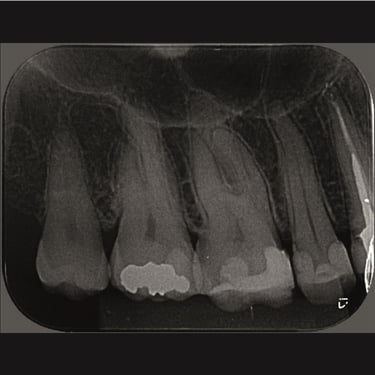

CASOS CLÍNICOS ENDO

Abaixo você encontra fotos de alguns dos tratamentos realizados.